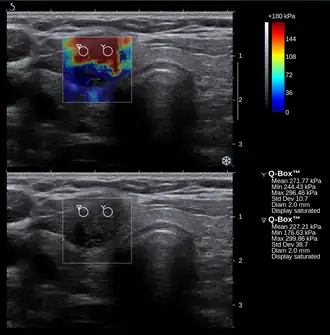

Conventional ultrasonography (lower image) and elastography (supersonic shear imaging; upper image) of papillary thyroid carcinoma, a malignant cancer. The cancer (red) is much stiffer than the healthy tissue.

Nowadays, the medical imaging modality of elastography can also be used to determine the stiffness of tissues. Manual palpation has several important limitations: it is limited to tissues accessible to the physician's hand, it is distorted by any intervening tissue, and it is qualitative but not quantitative. Elastography is able to overcome many these challenges and improve on the benefits of palpation.

Elastography is a relatively new technology and entered the clinic primarily in the last decade. The most prominent techniques use ultrasound or magnetic resonance imaging (MRI) to make both the stiffness map and an anatomical image for comparison.